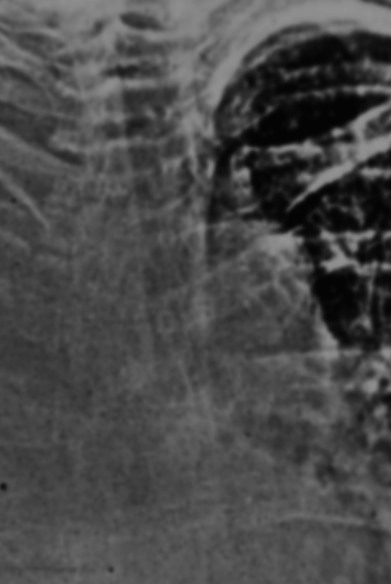

На второй рентгенограмме вероятно опухоль правого легкого. Но оценить легочный рисунок слева мне сложно. Тоже кажется что диссеминация. Хотя подобную рентгенологическую картину я наблюдала у пациентов с алкогольным циррозом печени после неоднократных пункций все расправлялось.

На правом снимке смущает плохая дифференциация, а местами и отсутствие таковой 10 ребра. "Газовый пузырь желудка" совсем не дифференцируется. Кажется мне, что и с некоторыми грудными позвонками - "кашка". Рискну предположить наличие на правом изображении  параканкрозного выпота.

По всей видимости, "на правом снимке", наряду с выпотом, можно предположить наличие ателектазированной нижней доли правого лёгкого, ибо при наличии такого количества выпота справа, средостение ведет себя довольно прилично, находится там, где положено.

На правом снимке вверху есть плевральное окно, на левом его нет - там намного больше жидкости. Мне легко, я знаю цитологию и анамнез. Справа - год назад удалена молочная железа. Слева - клиника пневмонии.

Правый снимок -плеврит воспалительной природы, пневмония, благополучный исход

На правом снимке - удивительно маленькие лопатки! А в позвоночнике - деф спондилоз, распространенный